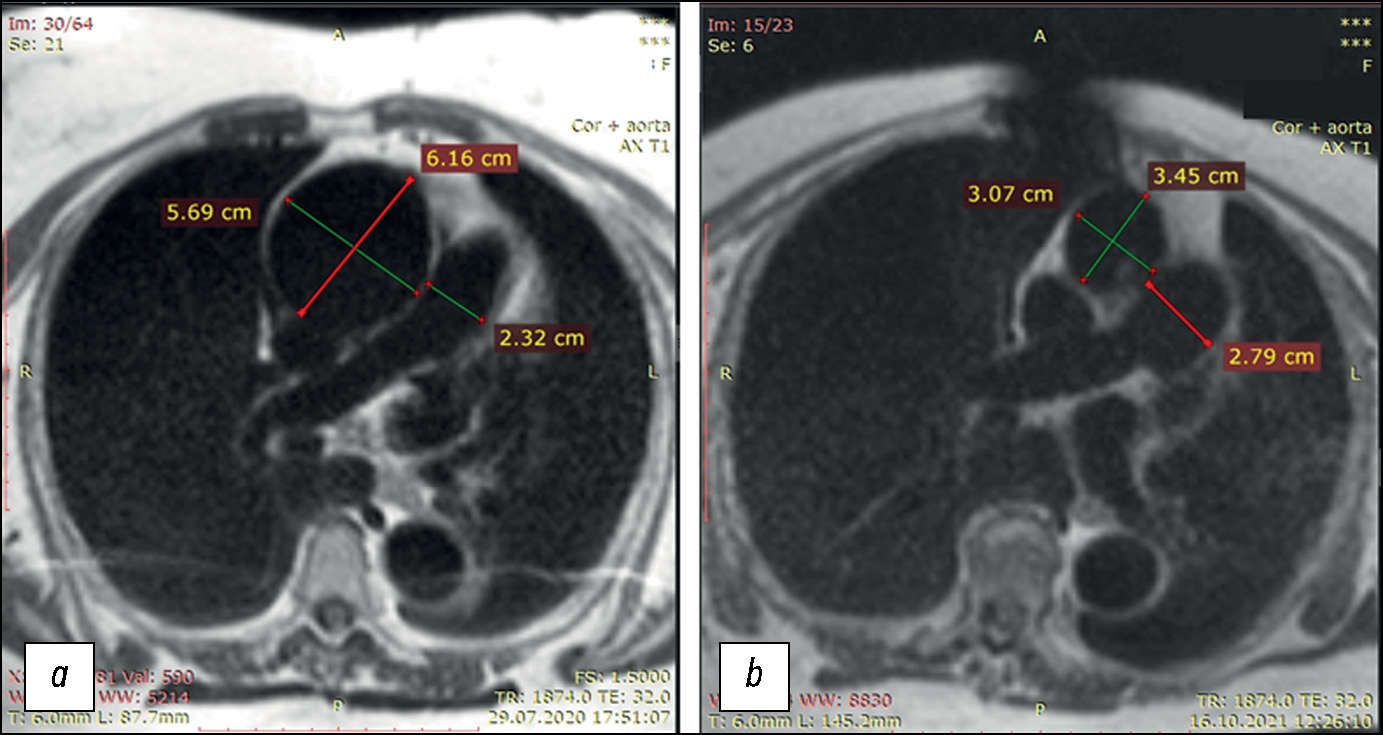

Optimization of left ventricular lead implantation based on combined myocardial perfusion scintigraphy and computed tomography data

Abstract

BACKGROUND: Successful cardiac resynchronization therapy in patients with chronic heart failure critically depends on the selection of the optimal implantation site for the left ventricular lead. A hybrid imaging approach combining cardiac venous computed tomography and myocardial perfusion scintigraphy may assist in identifying the target vein and improve procedural efficacy.

AIM: The work aimed to evaluate the feasibility of a multimodal imaging approach for optimizing left ventricular lead implantation in cardiac resynchronization therapy.

METHODS: It was a prospective, observational, single-center, non-randomized controlled study. Patients with chronic heart failure and indications for cardiac resynchronization therapy in accordance with current guidelines were enrolled. Prior to the procedure, the patients underwent computed tomography of the cardiac veins to visualize venous anatomy and myocardial perfusion scintigraphy to assess the extent of left ventricular perfusion impairment. The optimal site for left ventricular lead placement was identified using a three-dimensional reconstruction of the coronary sinus fused with myocardial perfusion scintigraphy data. To assess the effectiveness of the hybrid approach, a reference group was formed, in which cardiac resynchronization implantation was performed using the standard method, without preprocedural evaluation of coronary venous anatomy or myocardial scarring. Six months after cardiac resynchronization therapy, all patients underwent echocardiography to evaluate treatment effectiveness. Echocardiographic response was defined as a reduction in left ventricular end-systolic volume by ≥15% and/or an increase in ejection fraction by ≥5%.

RESULTS: The imaging group consisted of 40 patients with chronic heart failure, whereas the reference group included 30 patients with the same diagnosis. Six months after cardiac resynchronization therapy, a positive treatment response was observed in 33 patients (82%) in the imaging group, significantly higher than in the reference group (17 patients, 57%), p = 0.031. In the imaging group, the reduction in left ventricular end-systolic volume was statistically significant compared with the reference group and amounted to −52 [−71; −22.5] mL versus −21 [−64; −1] mL, respectively (p = 0.039). The increase in left ventricular ejection fraction was 7.5 [4.5; 15]% in the imaging group and 4.5 [0; 13]% in the reference group, with no statistically significant difference (p = 0.082).

CONCLUSION: The use of cardiovascular imaging methods, including cardiac venous computed tomography and myocardial perfusion scintigraphy, was associated with an increased proportion of responders to cardiac resynchronization therapy.